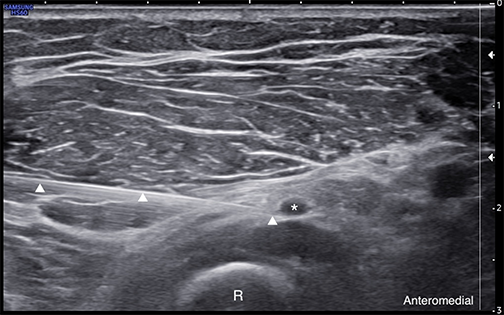

Labeled ultrasound-guided injection at the radial tunnel using a lateral-to-medial short-axis approach, with the needle tip visualized adjacent to the deep motor branch of the radial nerve. * = Deep motor branch of the radial nerve R = Radius Arrowheads = Needle